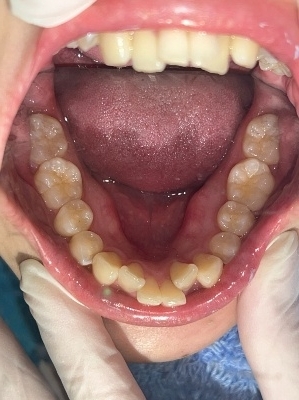

上顎

下顎